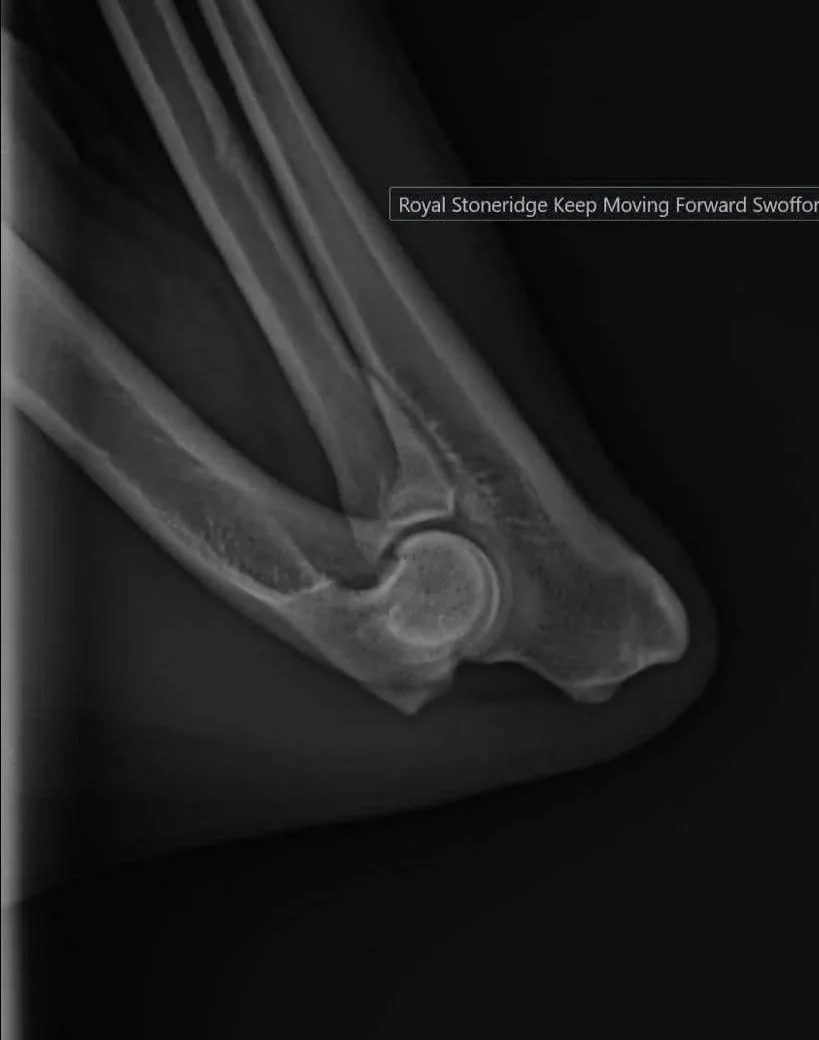

Elbow Dysplasia

Summary: Elbow dysplasia is recognized by an abnormal conformation of the elbow joint, leading to a painful grinding of bone-on-bone between the ball and the socket of the joint. Arthritis, mobility issues, and swelling at the elbow are common symptoms seen in dogs with this condition.  In affected individuals, both surgery or supportive care may be viable options, as recommended by your veterinarian.

Screening: Available in the US through the OFA database which will evaluate each elbow individually through radiographs taken by your vet and assign a grade to each elbow. Elbows may be unaffected (“normal”), unilaterally affected, or bilaterally affected. Elbows can be evaluated at two years of age or older.